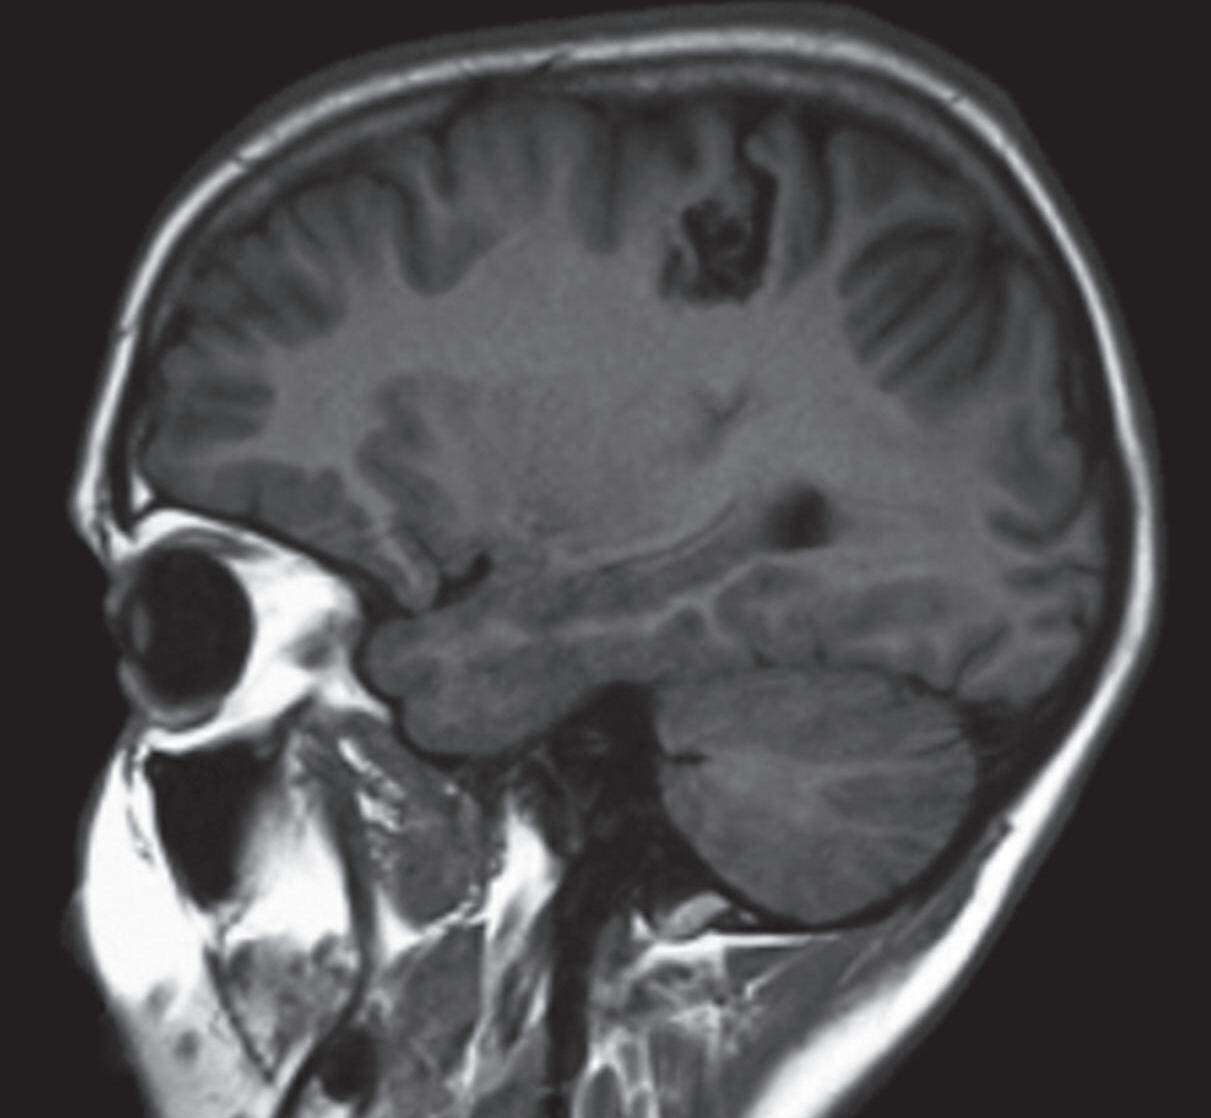

Fig. 1-8. (a-c) RNM T1 com contraste, cortes sagital (a), coronal (b) e axial (c) demonstrando MAV não rota com nidus localizado no lobo occipital à esquerda (setas longas). (d) Arteriografia digital cerebral com injeção de contraste via carótida direita (AP) mostrando a contribuição da carótida direita na irrigação da MAV contralateral. (e,f) Com injeção de contraste via carótida esquerda, em Perfil e AP respectivamente, observa-se nidus compacto nutrido por ramos da artéria cerebral média à esquerda e a veia de drenagem precoce se dirigindo para o seio sagital superior. Projeções em AP (g) e em perfil (h) demonstrando a contribuição do sistema vertebrobasilar por meio de ramos distais da artéria cerebral posterior à esquerda e drenagem para os seios sagital superior e sigmoide à esquerda (setas curtas).